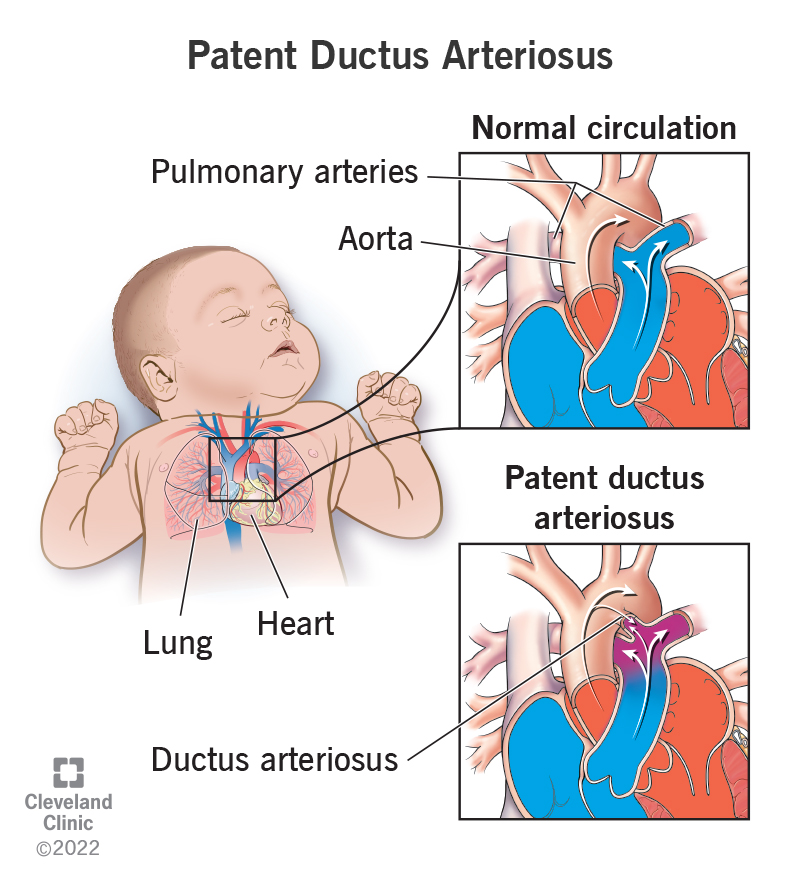

PDA Pathophysiology and Anatomy

What is PDA in Newborn Babies

What is PDA in Newborn Babies

Patent Ductus Arteriosus PDA in the newborn

Patent Ductus Arteriosus PDA for Parents Nemours Kidshealth